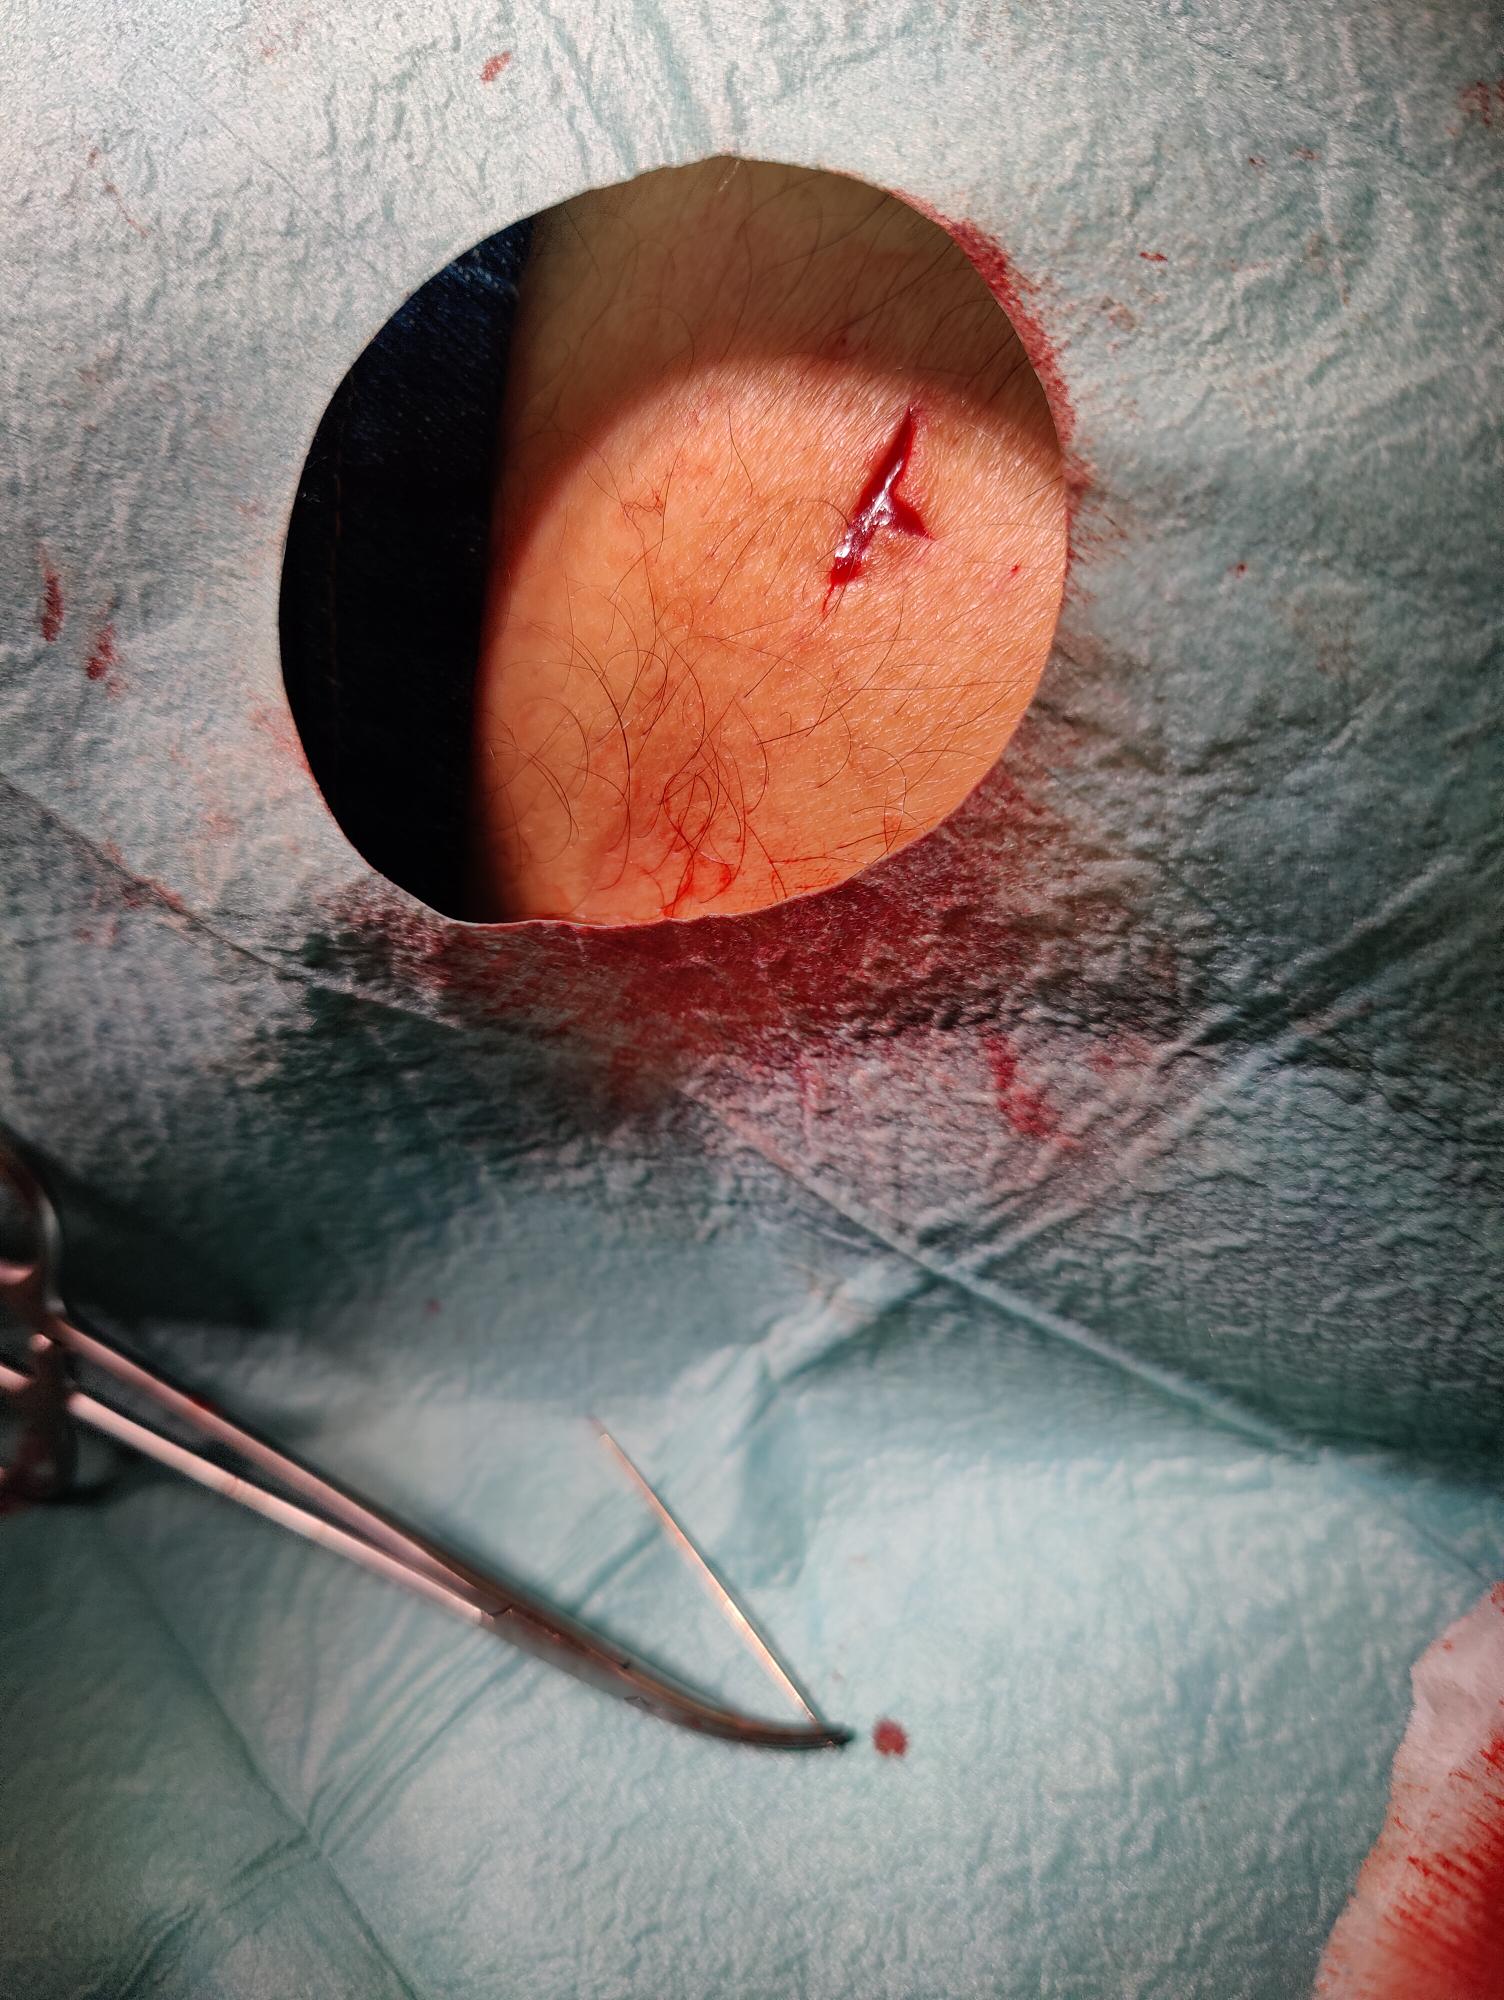

Tras anestesia local, se procede a realizar incisión y extracción de la aguja, encontrándose íntegra.Evolución

Tras el procedimiento se suturó la herida y fue dado de alta a domicilio.